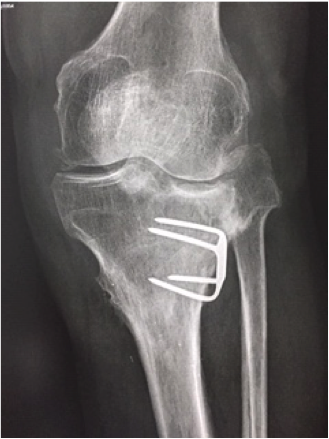

Technique Ligamentoplastie du LCA par une plastie DIDT mixte continue avec plastie latérale originale : description technique et résultats à long terme (10 ans) , Stéphane Costes Service de chirurgie orthopédique et traumatologique, CH Robert Boulin, 112 Rue de la Marne, 33500 Libourne, France 🖂 stephane.costes@ch-libourne.fr , Pierre Meynard Service de chirurgie orthopédique et traumatologique, CH Robert Boulin, 112 Rue de la Marne, 33500 Libourne, France N°300 - Janvier 2021 ● 18 min de lecture